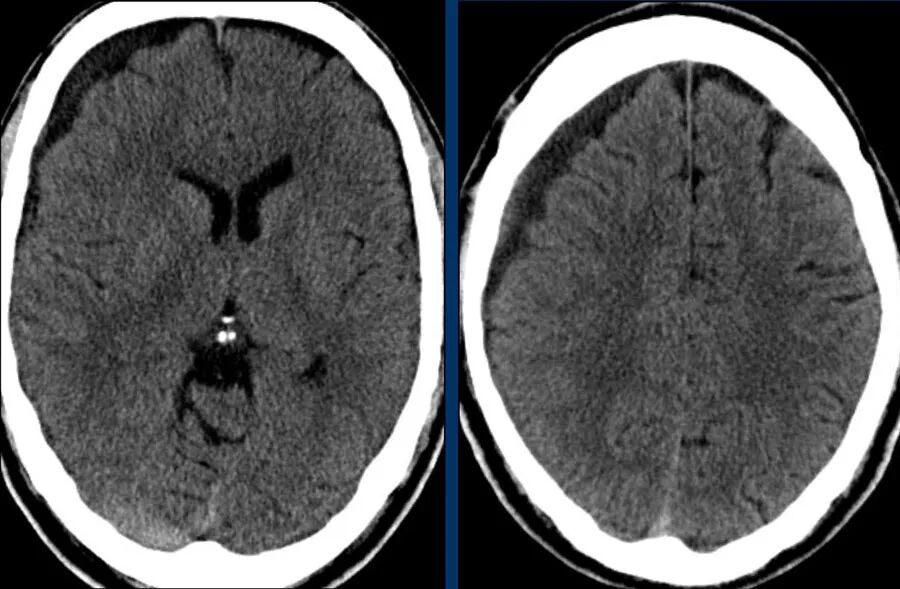

下图 一位46岁的男子骑摩托车时受伤。

瞳孔无反应性,瞳孔扩张。

CT:额叶点状出血。

继续做核磁共振成像

弥漫性轴索损伤(DAI)MRI表现

- 累及皮质下区、胼胝体、右侧丘脑和壳核、脑干、小脑脚和右侧小脑半球。

- 轻度全球萎缩。

MRI可准确诊断DAI,包括T2*GRE或SWI。

DAI在颅脑损伤患者MRI上的存在,更有可能导致不良的功能结局。